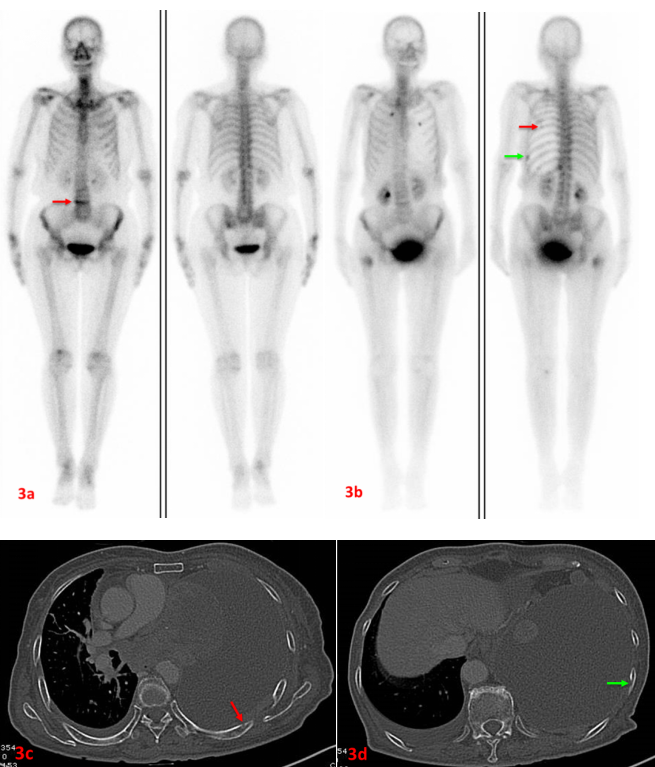

老年女性,左肺腺癌。初次ECT(3a圖)示L4(3a紅箭)代謝異常增強,考慮壓縮性骨折。7個月后復(fù)查ECT(3b圖)示雙側(cè)多根肋骨、右側(cè)股骨上端代謝異常增強,考慮多發(fā)骨轉(zhuǎn)移。L4代謝較前片明顯減低。同期CT檢查可見左側(cè)第7后肋(3c紅箭)、左側(cè)第9后肋(3d綠箭)溶骨性破壞。此病例證實了ECT定期復(fù)查的必要性,建議惡性腫瘤患者3-6個月復(fù)查一次。